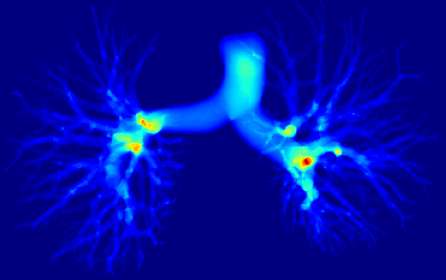

However, current state-of-the-art methods of lung organ segmentation still face several challenges and aspects for improvement. Firstly, the unlimited voxel values, multi-site imaging discrepancy and class imbalance in lung organ images can lead to false-negative and leakage issues in prior segmentation methods, which badly influences the critical early diagnosis of imperceptible lung diseases, e.g., lung fibrosis, nodule and hypertension, etc. Secondly, the presence of numerous slender branches, e.g., bronchioles and arterioles, which are easily lost during the recycled down/up-sampling procedure in Fig. 1, can result in discontinuity, detail loss, and coarse mask predictions. Thirdly, most CNN-based medical segmentation methods treat all points equally during the mask rendering stage, overlooking the vulnerability of border points in Fig. 1 (f) and the importance of explicit border modeling. Lastly, while Vision Transformer (ViT) has shown promise in computer vision tasks [1, 4], its quadratic operation complexity limits its application in 3D high-resolution CT images due to hardware constraints. Meanwhile, most specific datasets for medical image analysis are small and scarce due to laborious manual annotation and privacy protection, which badly restricts the potential of transformer-based top-tier methods.

2.2 Global-Local Cube-tree Fusion

where [0, 1] are the learnable coefficients to balance the importance of each feature; (6) we lastly add the feature to the relative position embedding features (retaining the topology information for inductive bias) for the voxel-wise decoding and refined prediction. Obviously, our proposed global-local cube-tree fusion module focuses merely on all border vulnerable points in Fig. 1(f) rather than all regular dense points in Fig. 1(c), which is more related to the lung organ regions. Experimental results demonstrate the efficacy of this design.

Ablation studies. To verify the efficacy of each module, we perform the thorough ablation studies in supplementary Tables 3-5 and Figs. 7-8. In Table 3, the 2-th row on lung fibrosis dataset with the proposed FA-based transformer-like backbone achieves the largest 2.24% CCFs, verifying the efficacy of fusing fuzzy sets and deep network to diminish the uncertainty in feature representations significantly. The 3-th row with GLCF module indicates 1.02% CCFs, proving that we only need to focus much on the very hard BVP rather than all regular dense points, which provide the most important losing information of discontinuity or details in the network down-sample operation. Since we only extract the BVP to render, it can suppress the redundant background to further solve the severe class imbalance issue of foreground and background voxels. Supplementary Table 4 evidences the efficacy of GLCF module which improves the border accuracy obviously by 4.72%. In Table 5, the 2-th row with FA-based transformer-like backbone improves the DBR significantly on the terminal (1.8%), small (1.25%) and medium (1.65%) branches except the large trachea (-1.03%), for most uncertainty in the feature representations is from the terminal, small and medium branches that are too thin and hard to be discerned while annotating. The 3-th row with GLCF module realizes the significant promotion of DBR on the small (2.02%), medium (2.02%) and large (3.09%) branches, which is consistent with Fig. 8 to overcome the issue of detail loss in the network down-sample operation and render the BVP effectively. Supplementary Fig. 7 elucidates that our FA-based transformer-like backbone can enhance the feature representations of lung organs significantly.